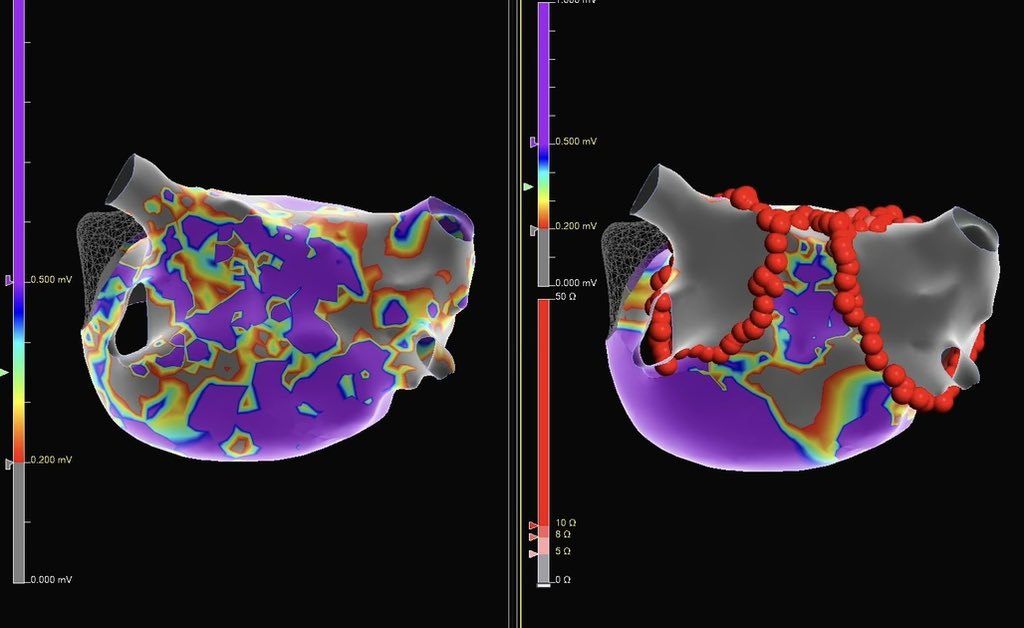

Is #PulseFieldAblation replacing RF Ablation?

Dr. Kristopher Heinzman & @pkothapalliMD explore its clinical promise, training risks & how EPs decide which patients fit PFA vs RFA.